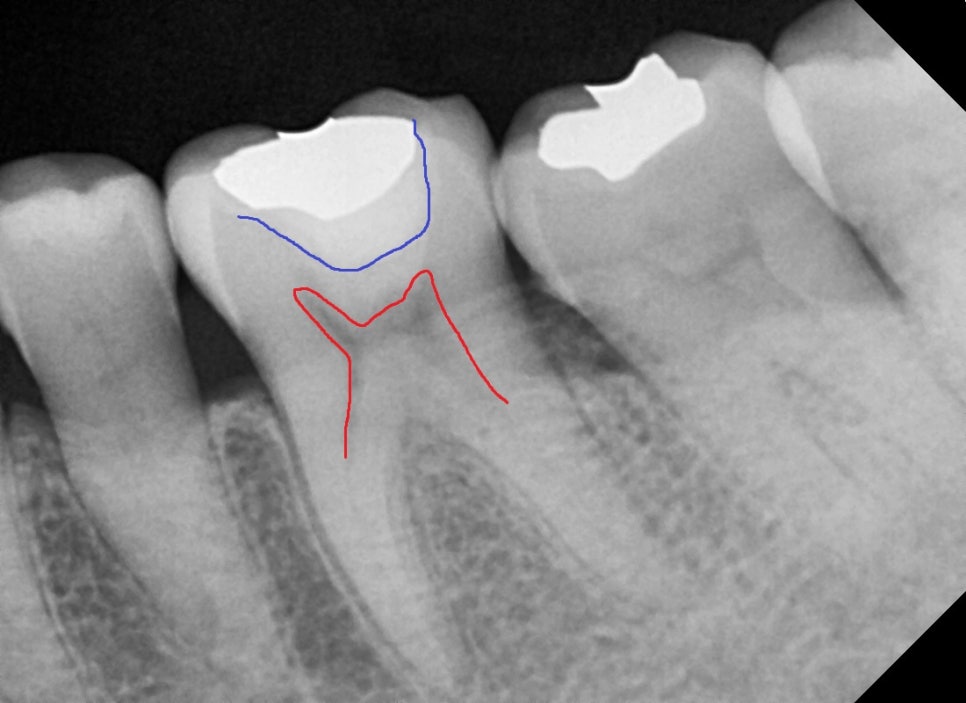

우측의 사진을 보면 과거에 처음 치료 하셨을 당시에도 깊은 충치를 치료 하신걸로 보여집니다.

빨간색은 치아 신경의 상방 경계부이며, 파란색선은 금 인레이 하방에 충전물질의 경계가 보입니다.

사진상으로는 과거 충전물질을 제거 하면 1mm정도의 거리가 남을것으로 예상되어집니다.

환자분께 금 인레이와 하방 우식을 제거해 보고 너무 깊을시 1차적으로 MTA를 사용하여

신경과 가까운 부분을 진정 시켜 신경치료 없이 치아를 크라운으로 치료하자고 설명을 드렸습니다.